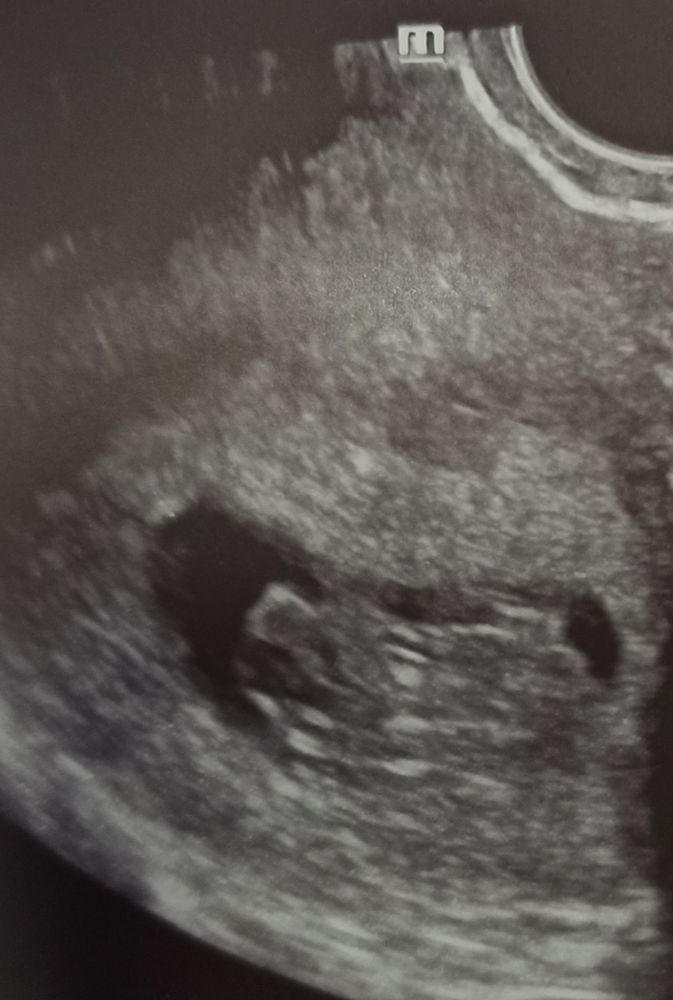

УЗИ на 50 дпо(9+1) ❤🤞🤞🤞

По УЗИ сегодня 05.04.2024г. всё хорошо, растем: ПЯ 51 мм, ЖМ 5,5 мм, КТР 26 мм, ЧСС 176 уд/мин, киста ЖТ 29*26 мм.